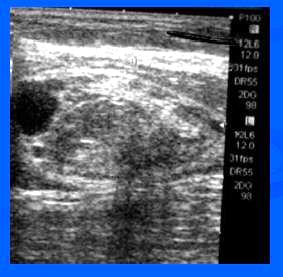

- UZ – heterogenní, izo a hypoechogenní, ostře ohraničené ložisko

- UZ – ohraničená anechogen.léze se solidní izoechogen.porcí